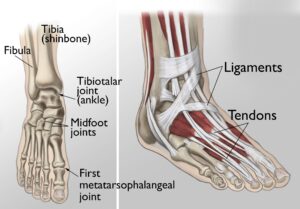

The foot and ankle play a critical role in supporting the body during standing, walking, and running. They provide balance, absorb shock, and facilitate movement. The ankle joint consists of three primary bones that enable up-and-down motion, while the foot comprises 28 bones and over 30 joints, allowing a broad range of movements. Many of these joints are protected by articular cartilage, a smooth, slippery tissue that ensures seamless movement by allowing bones to glide over one another. Surrounding the joints is the synovium, a thin membrane responsible for producing lubricating fluid that minimizes friction during movement. Ligaments, which are tough bands of tissue, connect the bones and stabilize the joints. Meanwhile, muscles and tendons provide the strength and support needed for mobility.

(Left) The joints of the ankle, midfoot, and big toe are commonly affected by arthritis. (Right) Ligaments connect the bones to each other, and tendons connect the bones to the surrounding muscles of the lower leg.